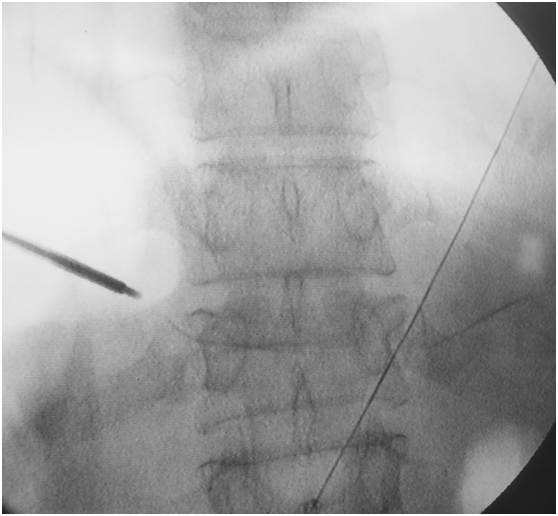

透视定位

穿刺位置的好坏,是决定手术质量的关键点。

术前透视定位伤椎

正位:从头往尾,最后一节有肋骨的为T12,从尾往头,两髂嵴联线齐第四腰椎棘突。

“三长四翘五肥大”:一般L3横突较长,L4横突短而上翘,L5横突较肥大。

侧位:楔形变,双凹形变椎体为伤椎。

例:T12上肋骨没发育。

注意:L5骶化,S1腰化,T12无肋骨的特例。

以椎弓根途径为例,皮肤进针点,为穿刺针针尖离椎弓根眼外缘1.5cm左右。

经椎弓根穿刺 ⬇